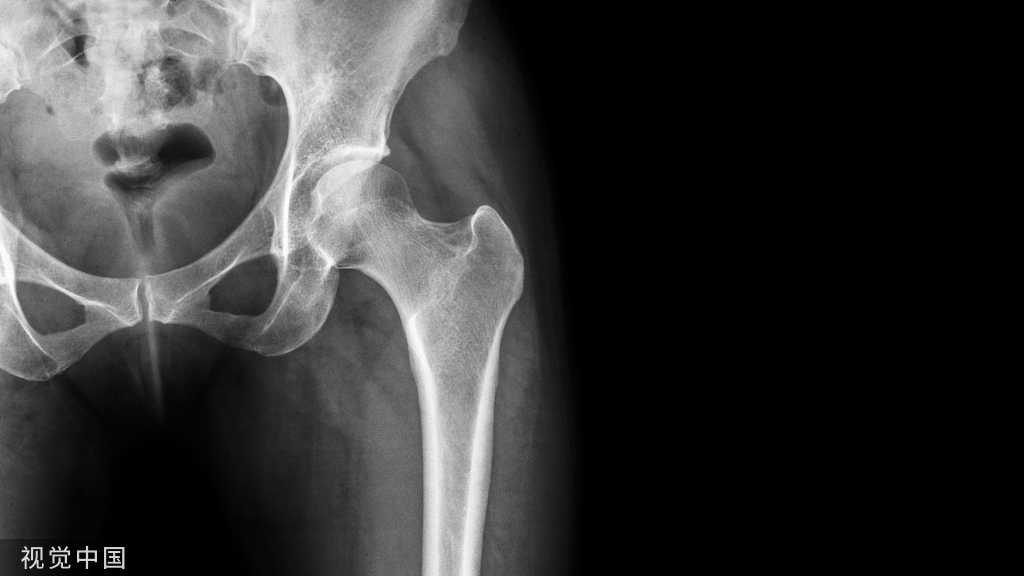

X线平片(首选方法):

- 骨盆正位片:尾骨尖端指向耻骨联合,且二者之间的距离是1~2 cm 。

- 能显示股骨近端、髋臼盂缘的骨性解剖异常。

X线表现

1、凸轮撞击型

直接表现:

- 股骨头颈联合处前上缘骨性突起:“ 枪柄样” 畸形。

- 非圆形的股骨头。

- 股骨头颈偏心距减小。

- α角增大。